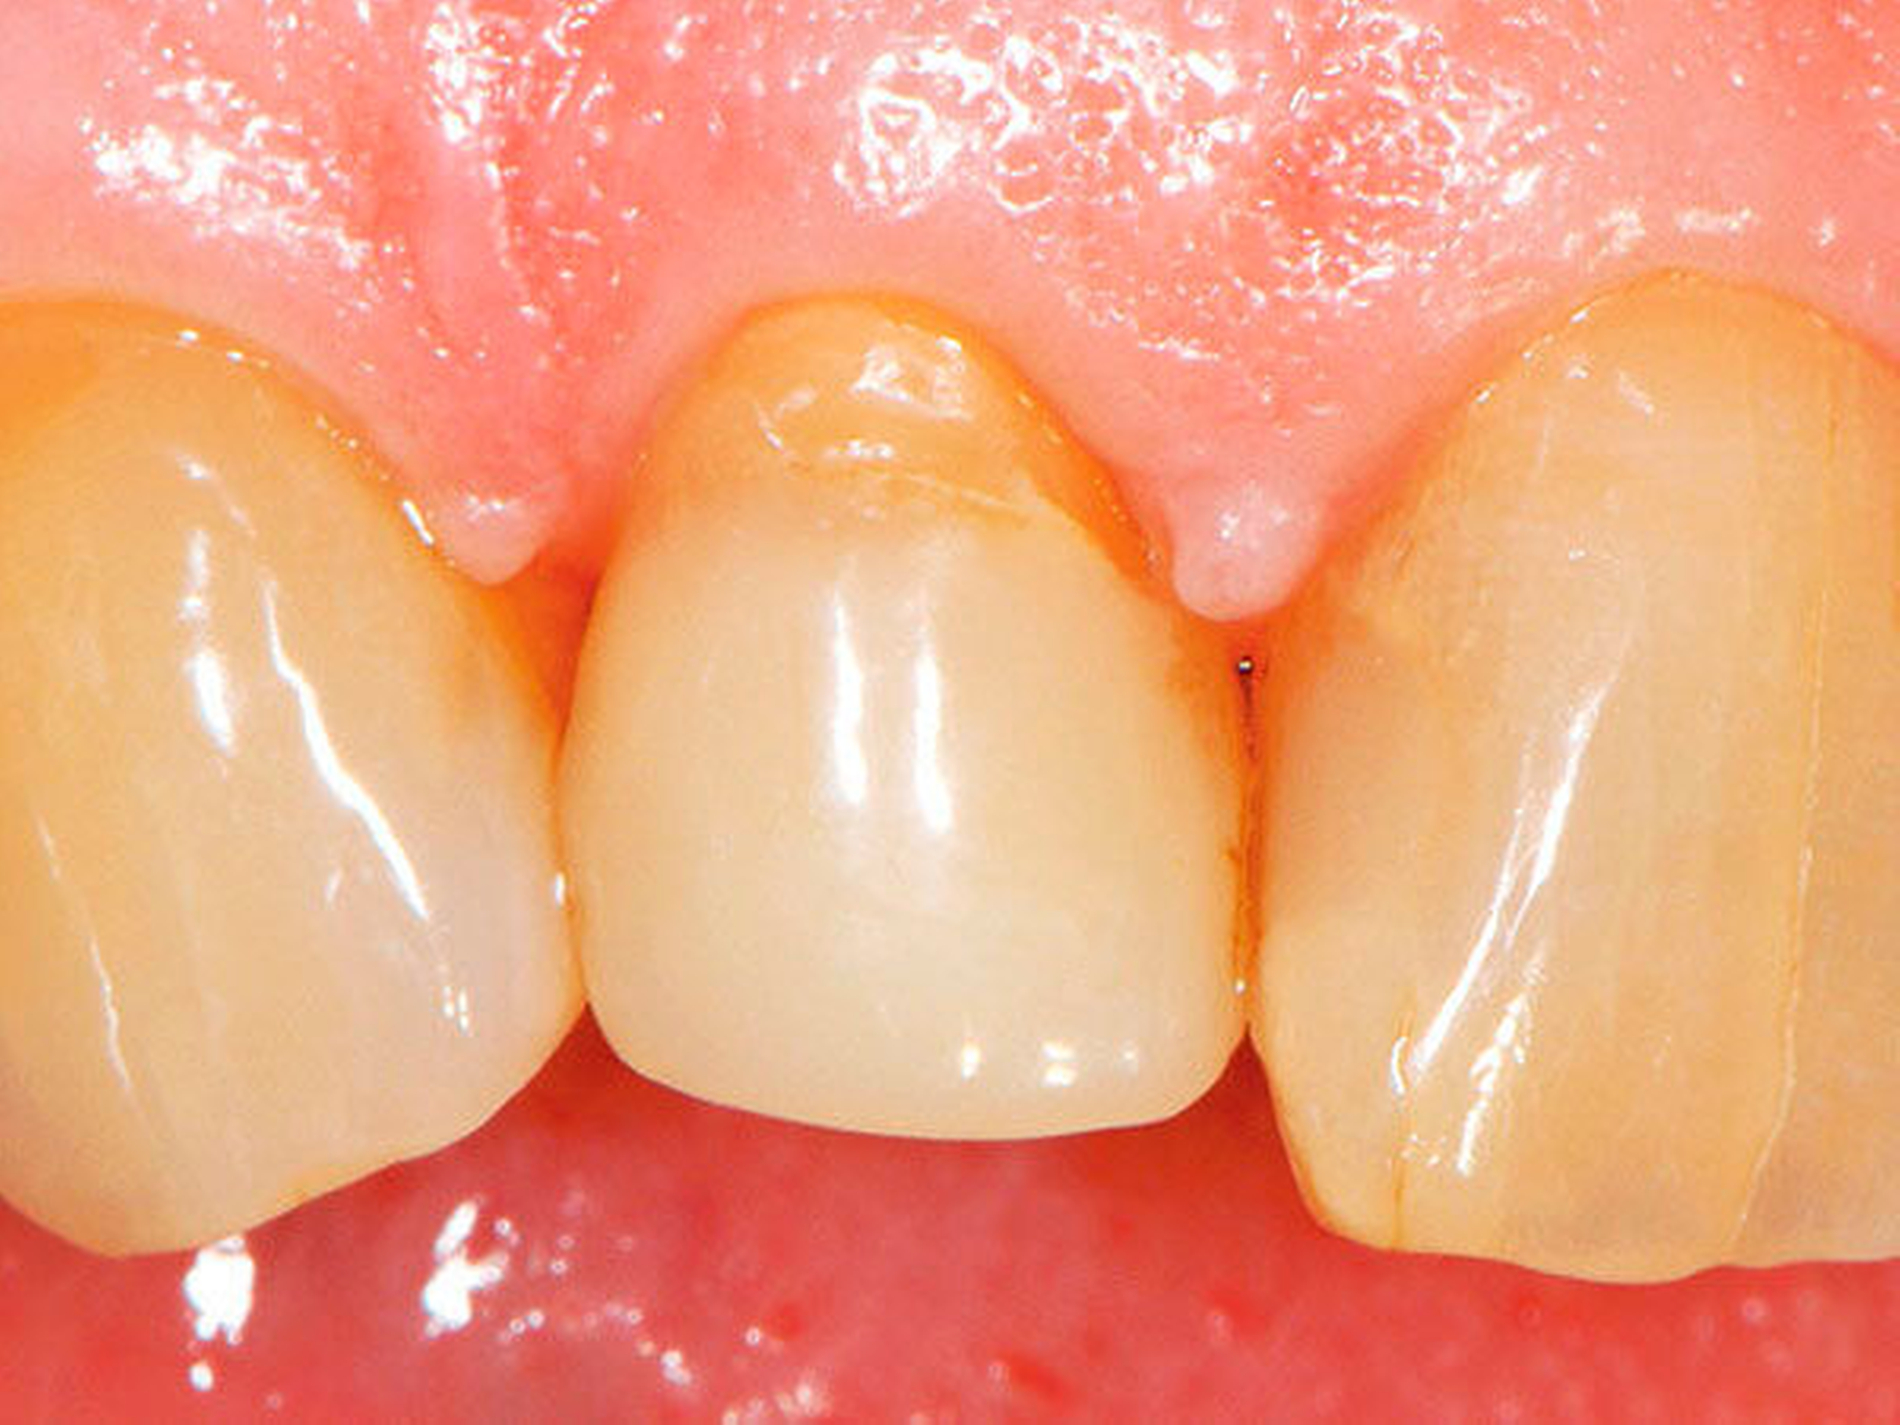

Abbildung 1a bis 1f: Direkte Überkronung im Frontzahnbereich (R1-Technik)

In den Abbildungen 1 bis 3 werden Optionen für frugale Interventionen auf restaurativem Sektor aufgeführt. Es handelt sich um direkte Vollüberkronungen im Frontzahnbereich (hier: hergestellt in R1-Technik / einphasig) (Abbildung 1), direkte Teilüberkronungen im Seitenzahnbereich (hier: hergestellt in R1-Technik / einphasig) (Abbildung 2), Reparatur-Restaurationen im Seitenzahnbereich (hier: hergestellt in R2-Technik / zweiphasig) (Abbildung 3). Technische Einzelheiten zur Vorgehensweise und den Ergebnissen sind an anderer Stelle beschrieben (Literatur siehe oben).

Am Beispiel von Abbildung 1 (stark zerstörte Zahnkrone eines Schneidezahns) kann das Prinzip der frugalen Intervention erläutert werden:

Früher wurde für die hier beschriebene Ausgangssituation folgendes Procedere gewählt:

Wurzelkanalbehandlung des vitalen Zahns als Voraussetzung für eine Stiftversorgung

Einsetzen eines Wurzelkanalstifts

Einsetzen einer indirekt gefertigten Stiftkrone

Durch die Erfolge der Adhäsiv- und Komposittechnik kann heute folgendermaßen vorgegangen werden:

Verzicht auf Wurzelkanalbehandlung / Erhaltung der Vitalität des Zahns

Verzicht auf Wurzelkanalstift

direkte minimalinvasive Kompositkrone (Verzicht auf indirekte Vorgehensweise)

Die potenziellen medizinischen und ökonomischen Vorteile dieser frugalen Intervention sind vielfältig:

Schonend: Die oralen Strukturen werden geschont und die Versorgung ist hinreichend stabil. Durch den Verzicht auf Wurzelkanalstifte wird das Wurzelfrakturrisiko reduziert. Zudem können Material-, Geräte- und Personalressourcen aus Praxis und Techniklabor, die beim klassischen Vorgehen anfielen, reduziert werden.

Bezahlbar: Hier ist anzumerken, dass die Kosten unter anderem von der zahnärztlichen Expertise abhängig sind: Zahnärzte, die mit direkten Restaurationen große Erfahrung haben, können zügiger und mit besserem Erfolg arbeiten als Kollegen mit geringerer Erfahrung auf diesem Gebiet; die Behandlung ist gleichwohl anspruchsvoll und deshalb nicht „billig“. Eine direkte Vorgehensweise kann, muss aber nicht automatisch zeit- und kostensparender sein als eine Versorgung mit indirekt hergestellten Werkstücken.

Gut genug: Ästhetische Feinheiten lassen sich bei direkten Restaurationen nicht immer in gleicher Perfektion einarbeiten wie bei indirekt gefertigten Kronen, auch die Stabilität des Hochglanzes lässt bei einigen Kompositpräparaten noch zu wünschen übrig. Andererseits erlauben die direkten Verfahren inzwischen mitunter sehr flexible Vorgehensweisen, die sich auch mit Farb- und Formkorrekturen von Zähnen kombinieren lassen. Die Erwartungen eines großen Teils der Patienten werden hinreichend erfüllt und die Nutzen-Risiko-Relationen wie auch die Aufwand-Kosten-Relationen erscheinen – wenn auch nicht durchgängig – so doch zumindest in vielen Fällen günstig.